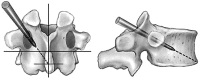

Cement reinforcement for the treatment of osteoporotic vertebral fractures is efficient mean with high success in pain release and prevention of further sintering of the reinforced vertebrae; however, the technique does not allow to address the kyphotic deformity. Kyphoplasty was designed to address the kyphotic deformity and help to realign the spine. It involves the percutaneous placement of an inflatable bone tamp into a vertebral body. Restoration of VB height and kyphosis correction is achieved by inflation of the bone tamp with liquid. After deflation, a cavity is created that eases the cement application. The potential of kyphosis reduction is given in fresh fractures with a range of 0-90% for height restoration and absolute correction of the kyphotic angle of 8.5 degrees. The cavity formation, on one hand, and the different cementing technique leads to lower risk for cement extravasation. An alternative method for kyphosis correction represents the so-called lordoplasty where the adjacent vertebrae are reinforced first and with the cannulas in place acting as a lever the reduction of the collapsed vertebra can be performed. The results with respect to kyphosis correction are superior in comparison with a kyphoplasty procedure.